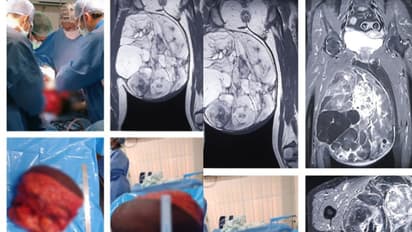

തൃശൂർ: 10 കിലോ ഭാരമുള്ള മുഴ കാരണം നടക്കാന് കഴിയാതെ വന്ന 61കാരിയ്ക്ക് ആശ്വാസമേകി തൃശൂര് മെഡിക്കല് കോളേജ്. 6 മണിക്കൂര് നീണ്ട ശസ്ത്രക്രിയയിലൂടെ കാലില് നിന്നും ട്യൂമര് നീക്കം ചെയ്തു. കാലില് തുടയോട് ചേര്ന്ന് അതിവേഗം വളര്ന്ന 10 കിലോഗ്രാം ഭാരമുള്ള ട്യൂമര് സങ്കീര്ണ ശസ്ത്രക്രിയയിലൂടെ നീക്കം ചെയ്ത് തൃശൂര് സര്ക്കാര് മെഡിക്കല് കോളേജ്. ട്യൂമര് മൂലം നടക്കാന് പോലും ഏറെ ബുദ്ധിമുട്ടിരുന്ന 61 വയസുള്ള തൃശൂര് പുഴക്കല് സ്വദേശിനിക്കാണ് ശസ്ത്രക്രിയ നടത്തിയത്.

കാലില് തുടയോട് ചേര്ന്ന് അതിവേഗം വളര്ന്ന 30x30x15 സെന്റീമീറ്റര് വലിപ്പമുള്ള ട്യൂമറായിരുന്നു. കൂടാതെ രോഗിക്ക് ഹെപ്പറ്റെറ്റിസ് ഉണ്ടായിരുന്നതിനാല് അധിക മുന്കരുതലുകള് കൂടിയെടുത്തു. ഈ മാസം പത്താം തീയതിയാണ് ശസ്ത്രക്രിയ നടത്തിയത്. ആറു മണിക്കൂര് നീണ്ടുനിന്ന ശസ്ത്രക്രിയയിലൂടെയാണ് കാലിലേക്കുള്ള രക്തക്കുഴലുകള്, നാഡീഞരമ്പുകള് എന്നിവയ്ക്ക് ക്ഷതമേല്ക്കാതെ 10 കിലോ തൂക്കവും 30x30x15 സെന്റീമീറ്റര് വ്യാപ്തിയുമുള്ള, സോഫ്റ്റ് ടിഷ്യൂ സാര്ക്കോമ നീക്കം ചെയ്തത്.

രോഗി സുഖം പ്രാപിച്ചപ്പോള് അടുത്തഘട്ട ചികിത്സയ്ക്കായി റേഡിയോതെറാപ്പി വിഭാഗത്തിലേക്ക് മാറ്റുകയും, ഫിസിയോതെറാപ്പി വിഭാഗത്തിന്റെ കൂടി ഇടപെടലോടെ കാലിലെ പേശികളുടെ തളര്ച്ച പരമാവധി കുറച്ചുകൊണ്ട് സാധാരണ ജീവിതത്തിലേക്ക് തിരിച്ചു വരികയും ചെയ്തിരിക്കുന്നു. സ്വകാര്യ മേഖലയില് ലക്ഷക്കണക്കിന് രൂപ ചെലവ് വരുമായിരുന്ന ഈ ശസ്ത്രക്രിയ സര്ക്കാരിന്റെ വിവിധ സ്കീമുകളില് ഉള്പ്പെടുത്തി സൗജന്യമായാണ് ചെയ്തത്.